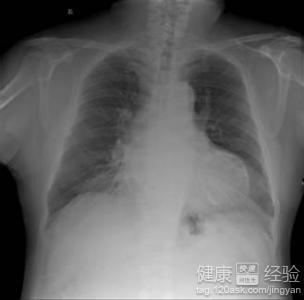

我父親今年已經有五十六歲了,在多年前患有過了甲減性的疾病,但是當時堅持治療三年多的時間,好不容易病症才恢復了。可是最近這一段時間,我父親突然感覺到胸口經常有陣陣疼痛的情況出現,而且精神狀況也比較差,整個臉都是慘白的,到醫院做了檢查後,發現是患有了甲減性心肌病,那到底像我父親這樣的甲減性的心肌病,應該要如何進行治療?

1通常當患者的甲狀腺的激素分泌過少或者是不敏感時,患者的機體代謝就會出現了下降的情況出現,組織器官的代謝需要及血液供應減少,心髒能量供應及耗氧量均減少,因此,心搏量減少,心率減慢,心排血量降低。